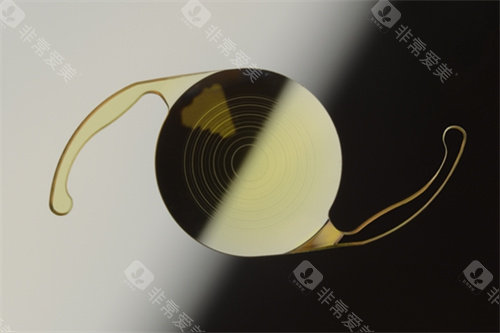

1. Aspira-aAY:双焦点性价比之选

技术亮点:采用双焦点衍射环设计,可同时提供远(5米外)与近(40厘米内)清晰视力,减少对老花镜的依赖。

适用人群:白内障合并老花眼患者,尤其适合需频繁切换视距的办公人群。

价格区间:单眼价格约5800-8000元,较蔡司双焦点晶体低。